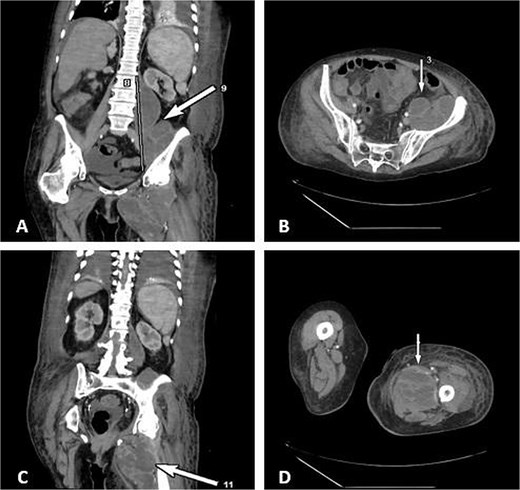

Due to the complex anatomy, a single access was deemed insufficient. Under real-time ultrasound and fluoroscopic guidance, a retroperitoneal approach was first used: an 18-G needle and guidewire were advanced in the left midaxillary line parallel to the iliac crest, followed by tract dilation and placement of a 12-G pigtail catheter into the psoas component. Subsequently, two additional 12G catheters were placed percutaneously via a femoral approach into the thigh extension (Fig. 2). In total, ~200 ml of purulent material was drained. The localization of the drains was confirmed by subsequent CT (Fig. 3).

Ultrasound and fluoroscopy show multi-access percutaneous drainage with one retroperitoneal and two femoral catheters. (A) Ultrasound-guided retroperitoneal puncture into the psoas collection. (B) Fluoroscopic image demonstrating catheter placement in the psoas component. (C) Ultrasound-guided puncture of the thigh extension. (D) Fluoroscopic confirmation of one retroperitoneal and two femoral drains in situ.